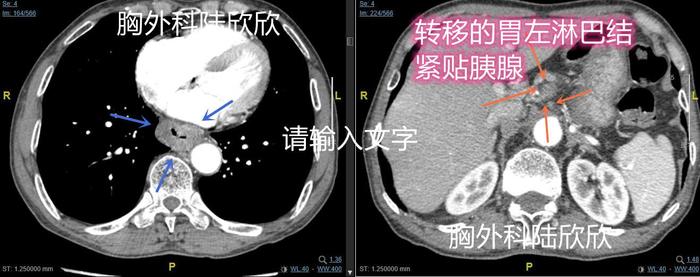

上图为图1。左边的图,心脏和降主动脉间可见食管下段癌较大,三个箭头指示。肿瘤中间的缝很狭窄,做胃镜检查时挤得慌,所以当时肿瘤有点出血。上面右边的图,肝脏和胃间可见一枚胃左淋巴结肿大,大约23×18mm,四个箭头指示。这个淋巴结是食管癌转移后肿大的

上图为图2。图2和图1是肿瘤和转移淋巴结的不同平面。上面右边的图,肝脏和胃间可见一枚胃左淋巴结肿大,三个箭头指示这张图是图1淋巴结的下极,所以没有第一张图显示的大。最右边的橙色箭头指示的是大淋巴结周围的小胃左淋巴结。这个大的胃左淋巴结手术难度较大。如果术前先化疗再手术,淋巴结缩小当然很好。但是如果化疗后淋巴结增大,将失去手术机会。所以,这个病人,我直接进行了手术治疗。